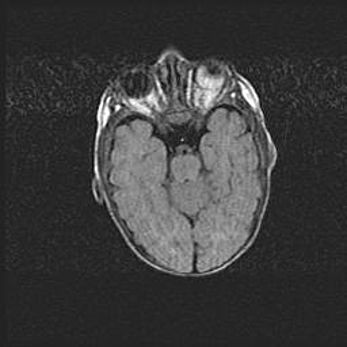

Наружная гидроцефалия с возможной атрофией височных областей.

Возраст: 28 дней

Вес: 3670 г

Пол: мужской

Окружность головы: 38 см

Срок гестации: 40 недель

Гидроцефалия головного мозга у новорожденных – это заболевание, которое характеризуется скоплением избыточного количества спинномозговой жидкости в желудочковой системе головного мозга в результате затруднения её перемещения от места выработки к месту поглощения в кровеносную систему или вследствие нарушения абсорбции. При открытой наружной форме гидроцефалии у новорожденных расширяются и переполняются субарахноидные пространства.

При нормотензивных  формах,  которые,  как  правило,  являются  следствием  перенесенных ишемических  повреждений  паренхимы  мозга,  возможно  сочетание микроцефалии  с нормотензивной гидроцефалией. В основе данных изменений лежит атрофия больших полушарий с преимущественной  локализацией  в  лобно-височных  областях.